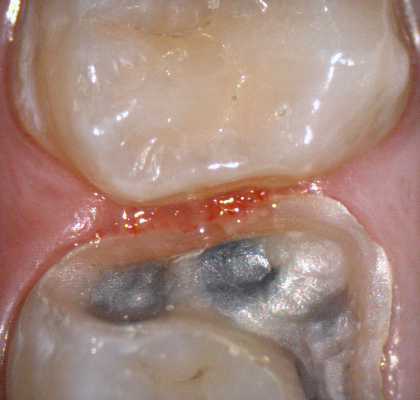

The following pictures depict the sequence of burs we recommend that you use to finish a preparation quickly. While patient is getting numb, take a quick look at the clearance you will need to reach proper material thickness. Once the quadrant is isolated with isolite and optragate, take an occlusal router bur and create a trough to gain the proper depth. Follow that with a flat disk, and you can quickly reduce the occlusal height.

A shoulder bur of .8 mm thickness can help you reduce the interproximal areas as well as the buccal and lingual margin lines. Before finishing the prep, place hemostatic agent like expasyl in the sulcus and place retraction cord. while it is setting, check your reduction. If you need more space, now is the time to reduce some more.